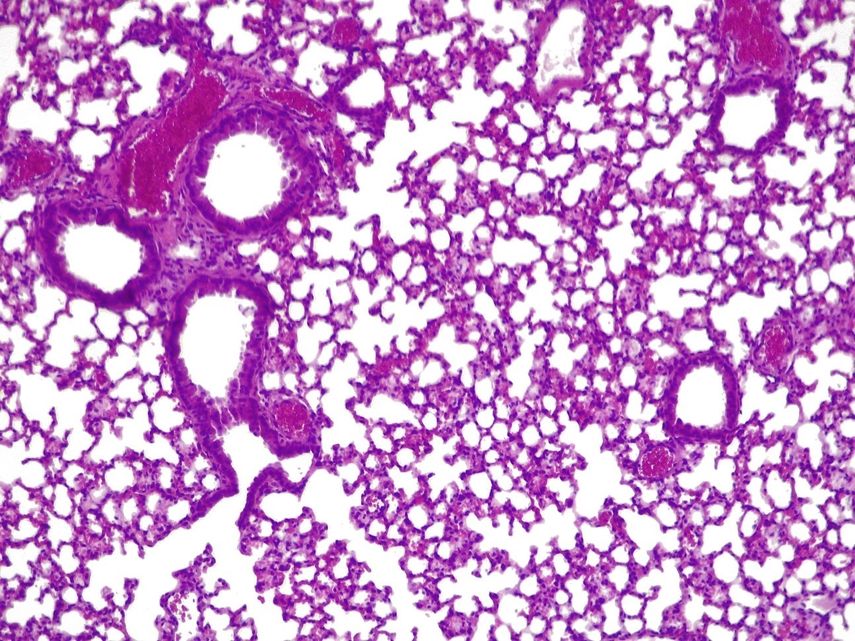

BARCELONA— Un equipo de investigación del Centro de Regulación Genómica (CRG) y Pulmobiotics ha diseñado una bacteria que actúa como una 'píldora viva' en el pulmón, y el tratamiento reduce las infecciones pulmonares agudas en ratones y duplica la tasa de supervivencia.

El tratamiento, cuyo estudio se ha publicado en la revista 'Nature Biotechnology', consiste en usar una versión modificada de la bacteria 'Mycoplasma pneumoniae' eliminando su capacidad patógena y adaptarla para que, en su lugar, ataque a 'presudomonas aerugionosa'.

La bacteria modificada se usa en combinación con dosis bajas de antibióticos que no serían eficaces por sí solas, y los científicos observaron que el uso del tratamiento en ratones redujo significativas las infecciones pulmonares.

Las infecciones causadas por 'presudomonas aerugionosa' son difíciles de tratar porque la bacteria vive en comunidades que forman biopelículas, que pueden adherirse a varias superficies del cuerpo, formando estructuras impenetrables que escapan al alcance de los antibióticos.

Las biopelículas de esta bacteria crecen en la superficie de los tubos endotraqueales utilizados por pacientes en estado crítico quienes, por lo tanto, requieren ventiladores mecánicos para respirar.

Esto causa neumonía asociada al ventilador (NAV), una afección que afecta hasta uno de cada cuatro (9-27%) pacientes que requieren intubación, y la incidencia supera el 50% en el caso de los pacientes intubados por covid-19 grave.

Para probar su eficacia, recogieron biopelículas de 'presudomonas aerugionosa' de los tubos endotraqueales de pacientes en unidades de cuidados intensivos, y mostraron que el tratamiento atraviesa la barrera y disuelve con éxito las biopelículas.